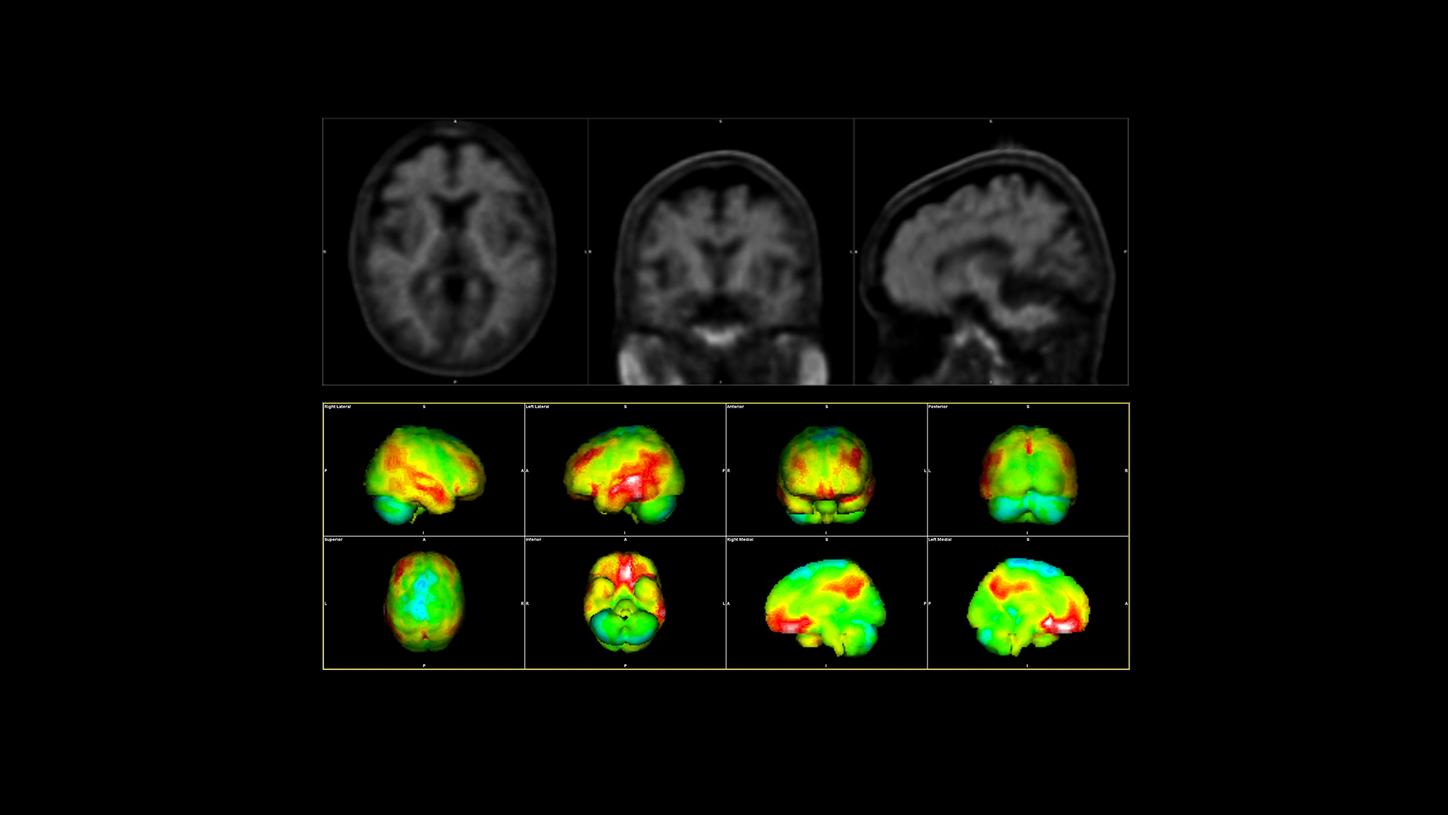

Ein typischer Amyloid-PET-Scan bei einem Alzheimer-Patienten: Die roten Bereiche sind die betroffenen Regionen im Gehirn.3